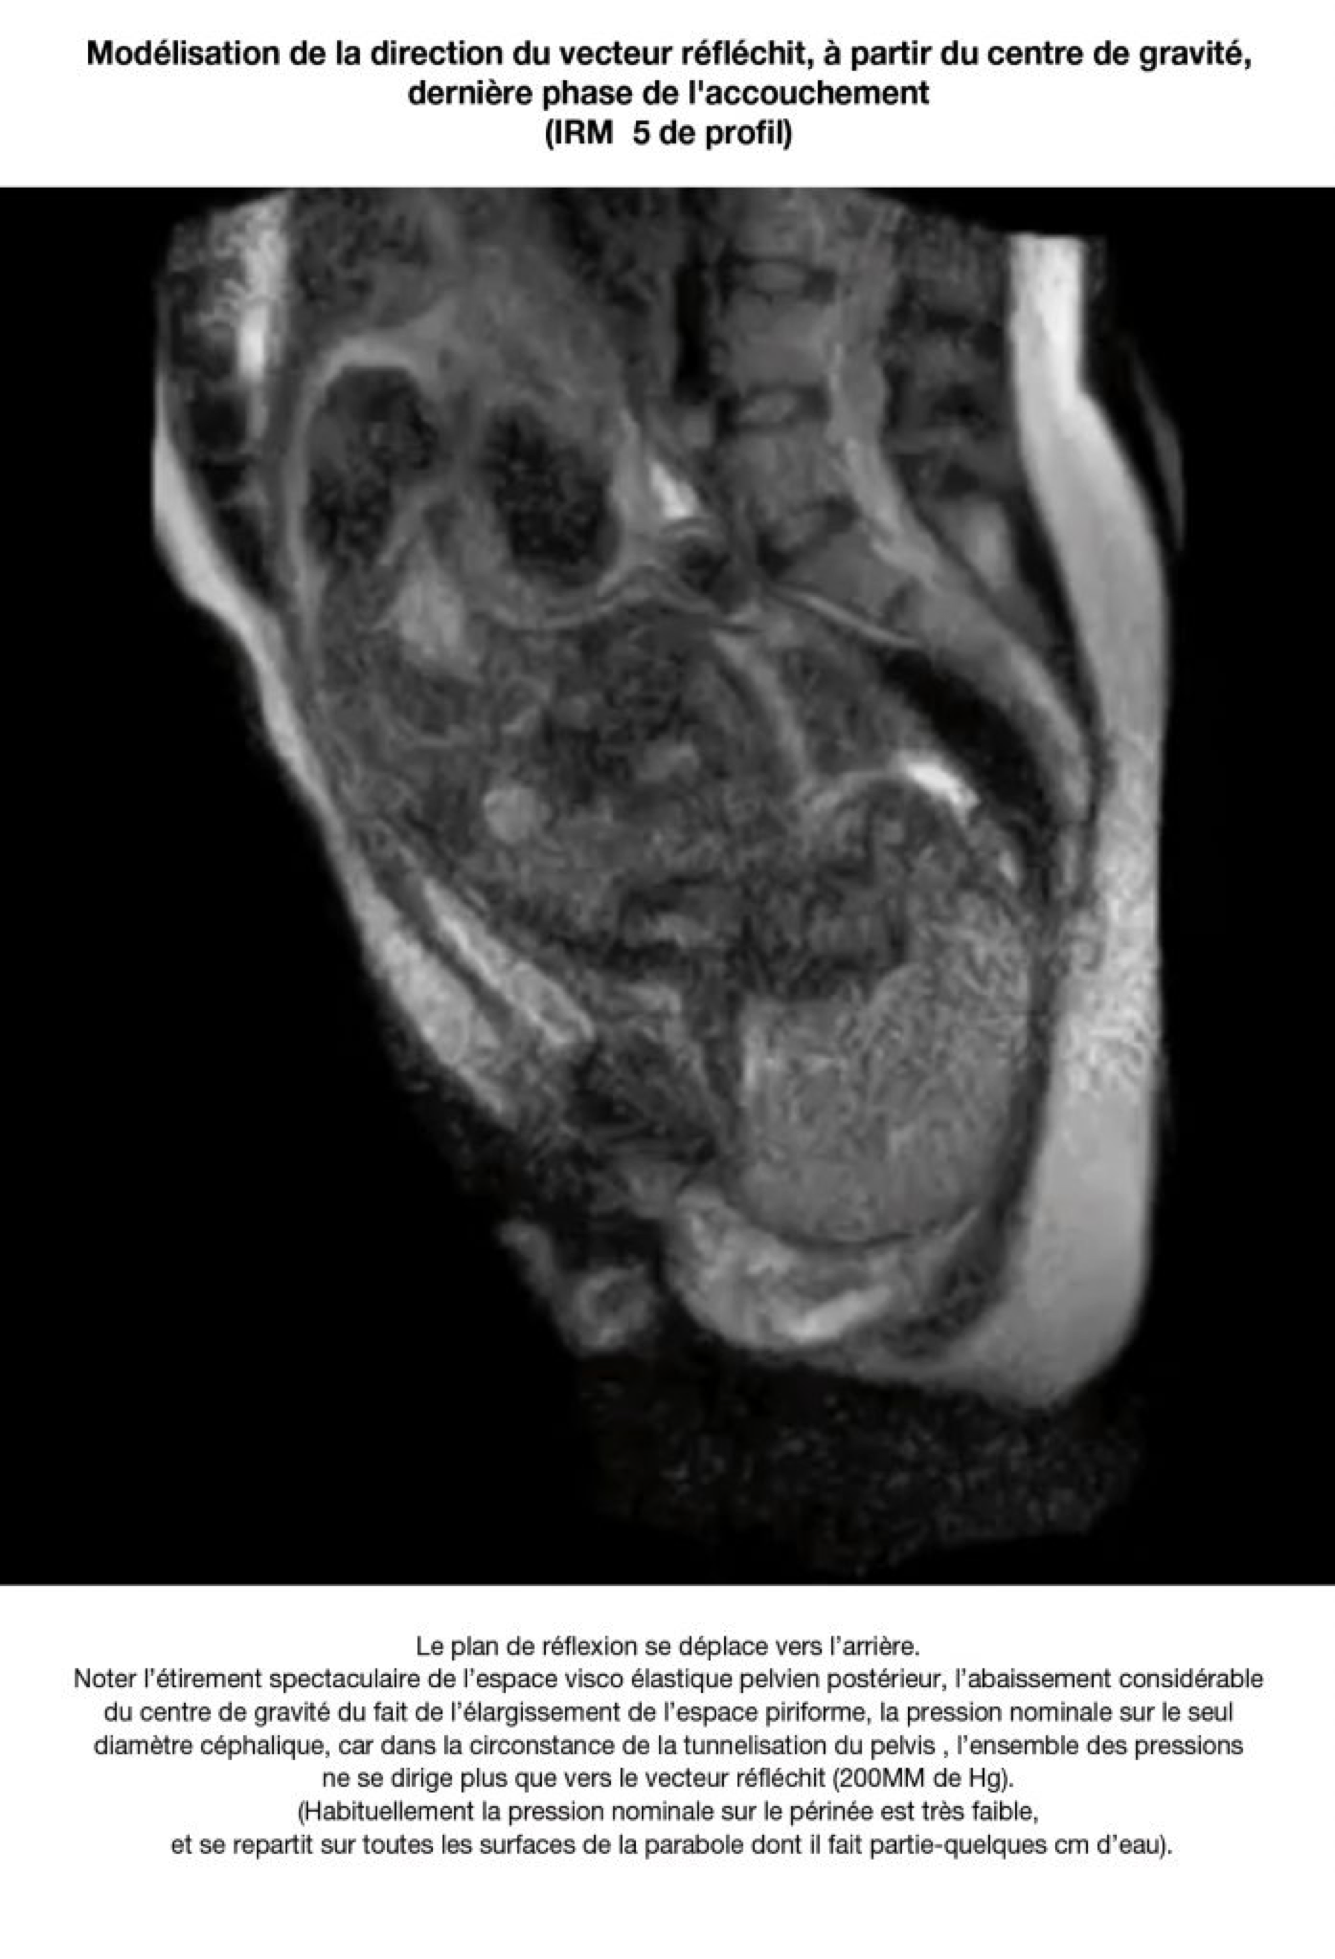

10. Périnée d’accouchement

LA PARABOLE SE RÉDUIT ET SES SURFACES DEVIENNENT VERTICALES AUTOUR DE LA PRÉSENTATION. LES VECTEURS DE PRESSION NE SONT PLUS RÉFLÉCHIS PAR DES PAROIS DEVENUES VERTICALES AUTOUR DE LA PRÉSENTATION CÉPHALIQUE. ILS S’ORIENTENT TOUS VERS LE FOND DU CYLINDRE .LA SURFACE DU FOND DU CYLINDRE PELVIEN EST TRÈS INFERIEURE À LA SURFACE DÉVELOPPÉE PAR LES PAROIS DU PARABOLOÏDE. TOUTE LA PRESSION ABDOMINALE SE DIRIGE VERS LE HIATUS UROGÉNITAL.

Au contraire la coupole s’élargit en cylindre et s’oriente en totalité vers le hiatus urogénital à la phase obstétricale de l’expulsion. Toute la puissance abdominale ne se dirige plus que vers « la sortie ».

Au contraire la coupole s’élargit en cylindre et s’oriente en totalité vers le hiatus urogénital à la phase obstétricale de l’expulsion. Toute la puissance abdominale ne se dirige plus que vers « la sortie »